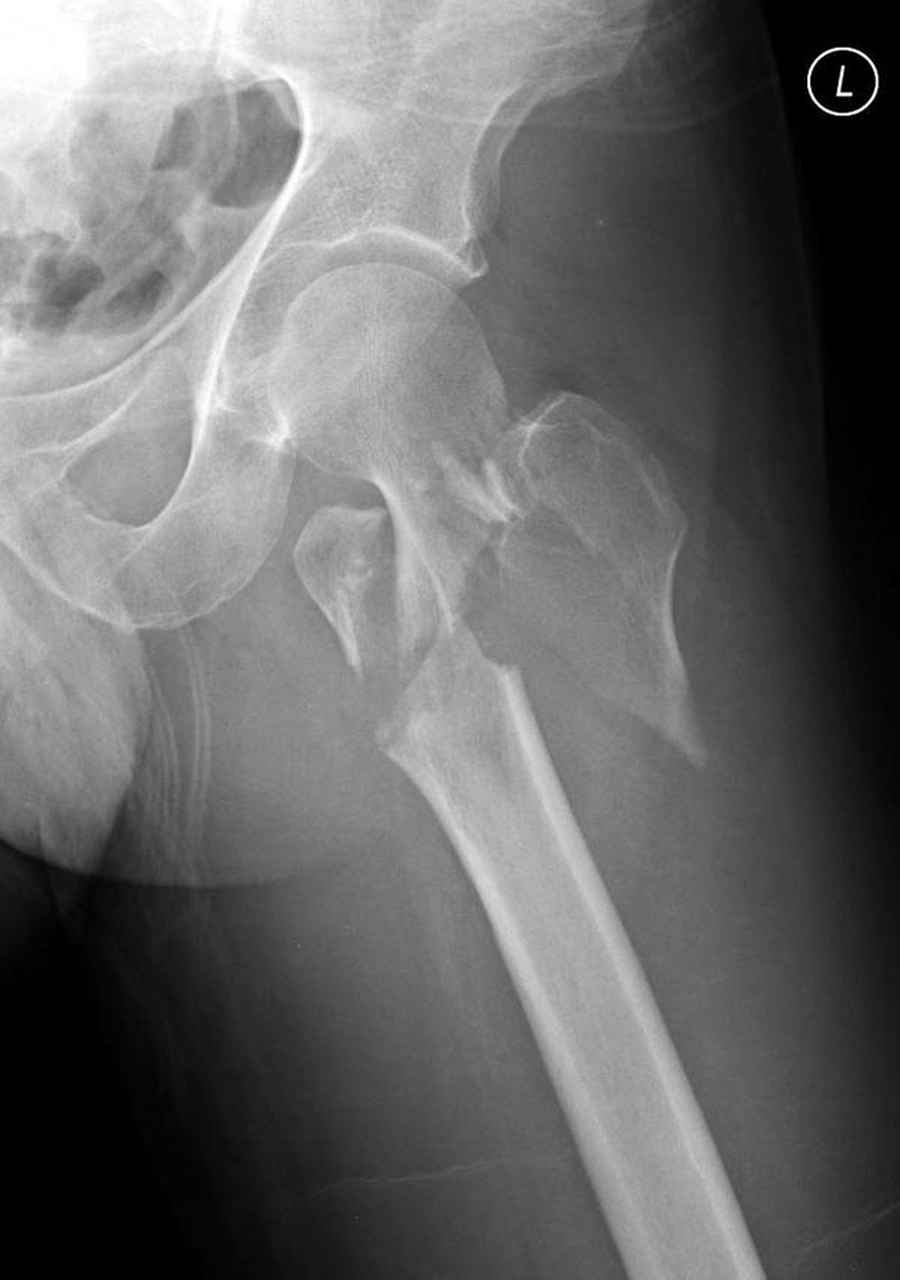

Здесь 83 года, травма в результате падения

Djoldas Kuldjanov, M.D.

Department of Orthopedic Surgery

St. Louis University